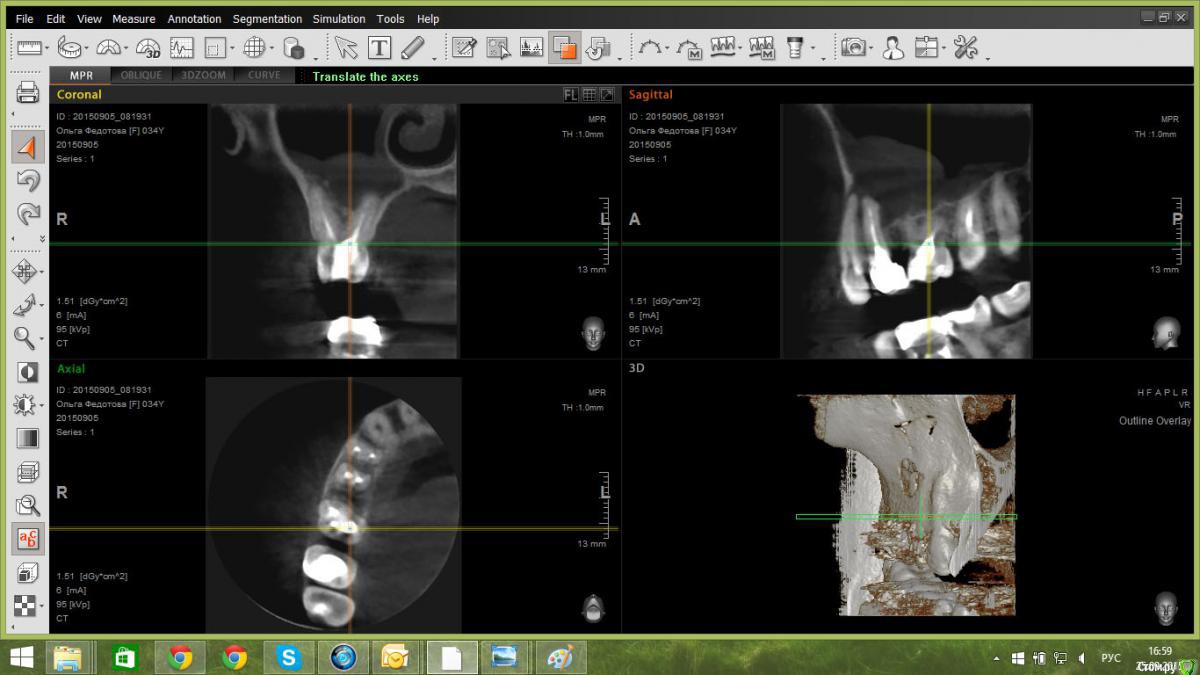

paciente Опубликовано 25 сентября, 2015 Поделиться Опубликовано 25 сентября, 2015 Здравствуйте!Посмотрите, пожалуйста, снимки. Начала болеть десна при нажатии, затем появилась небольшая припухлость щеки снаружи и достаточно сильная внутри, на десне, температура. Сделали КТ, диагноз - киста (зубы верхние справа, если правильно считаю, 4-й и 5-й), которая проросла в гайморову пазуху. Хирург сделал надрез в десне и поставил дренаж, припухлость спала. Прокололи линкомицин в течение недели, плюс прокапала в нос капли полидекса неделю. Есть два мнения хирургов:1. Вырвать два зуба, подождать месяц, сделать повторно КТ и дальше решать с лорами, что делать с пазухой. Подождать четыре месяца и ставить импланты.2. Обратиться в клинику со стационаром, удалить зубы и кисту (удаляет, как я поняла, хирург-стоматолог под контролем лора) зашить (?) образовавшееся отверстие в гайморовой пазухе, подождать десять месяцев и ставить импланты.Оба хирурга считают, что кости будет недостаточно и необходимо будет ее наращивать. Хирург номер два посоветовал для начала обратиться в районную поликлинику. Там хирург мне сходу сказал, что помочь мне не может и что диагноз "киста" невозможно поставить без пункции. На просьбу дать направление туда, где мне могут помочь, попросил принести описание КТ, т.к. он открыть снимок не может, у него нет компьютера. Описание КТ сделать не удалось - в клинике, где я его делала, нет стоматолога, в остальных местах мне отказались делать описание "чужого" КТ. Насколько я понимаю, если делать операцию в рамках ОМС, то это предполагает хождение по мукам из одного заведения в другое, где постоянно будут просить какие-то дополнительные бумажки. Если делать платно - опять же я не совсем понимаю, куда можно обратиться. Звонила в клинику МГМСУ на Вучетича, обхамили еще на попытке записаться, в ЦНИИС за два дня постоянных попыток дозвониться не удалось. Возможно, нужно идти к конкретному врачу, но я не знаю к кому. По состоянию: постоянная температура 37, слабость, прозрачные выделения из правой ноздри, головная боль.На руках диски с КТ и ортопантомограммой. Описания снимков и заключения врачей нет.Выложила принтскрины КТ и оптг. Если нужно, заархивирую КТ и выложу ссылку. Прошу посоветовать, что именно лучше сделать, а также клинику, а лучше врача в Москве. Огромное спасибо за ответ!!! Ссылка на комментарий

paciente Опубликовано 25 сентября, 2015 Автор Поделиться Опубликовано 25 сентября, 2015 Прошу прощения за глупые вопросы, но как выложить срезы 4 и 5 зубов? Я крутила, в основном, картинку в верхнем правом углу, она мне показалась самой информативной почему-то Что еще нужно покрутить, чтобы выложить то, что нужно? Ссылка на комментарий

paciente Опубликовано 25 сентября, 2015 Автор Поделиться Опубликовано 25 сентября, 2015 Как мне кажется, нужно перелечить зубы 24,25 качественно, хорошо.Александр, подскажите, пожалуйста, пропадет ли в этом случае киста из гайморовой пазухи? Дело в том, что когда я только обратилась по поводу слабой боли в десне, мне сделали оптг и сказали, что можно перелечить зуб под коронкой (25?): снять коронку, положить лекарство и менять его, пока не уйдет киста. Я взяла несколько дней на подумать и в этот период началось воспаление. В ближайшей к дому клинике сделали КТ и после того, как его посмотрели о лечении зубов уже речи не шло - только под удаление, причем два зуба. Если я правильно поняла врачей - там почти ничего не осталось от корней. Ссылка на комментарий